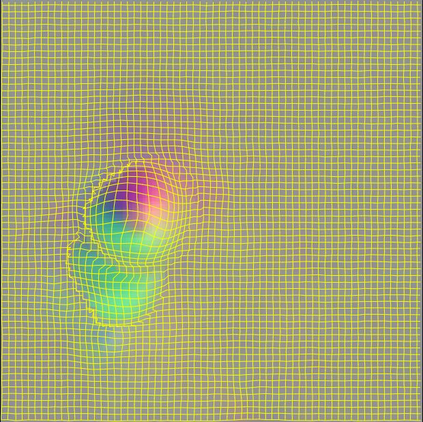

Image registration aims to establish spatial correspondence across pairs, or groups of images, and is a cornerstone of medical image computing and computer-assisted-interventions. Currently, most deep learning-based registration methods assume that the desired deformation fields are globally smooth and continuous, which is not always valid for real-world scenarios, especially in medical image registration (e.g. cardiac imaging and abdominal imaging). Such a global constraint can lead to artefacts and increased errors at discontinuous tissue interfaces. To tackle this issue, we propose a weakly-supervised Deep Discontinuity-preserving Image Registration network (DDIR), to obtain better registration performance and realistic deformation fields. We demonstrate that our method achieves significant improvements in registration accuracy and predicts more realistic deformations, in registration experiments on cardiac magnetic resonance (MR) images from UK Biobank Imaging Study (UKBB), than state-of-the-art approaches.